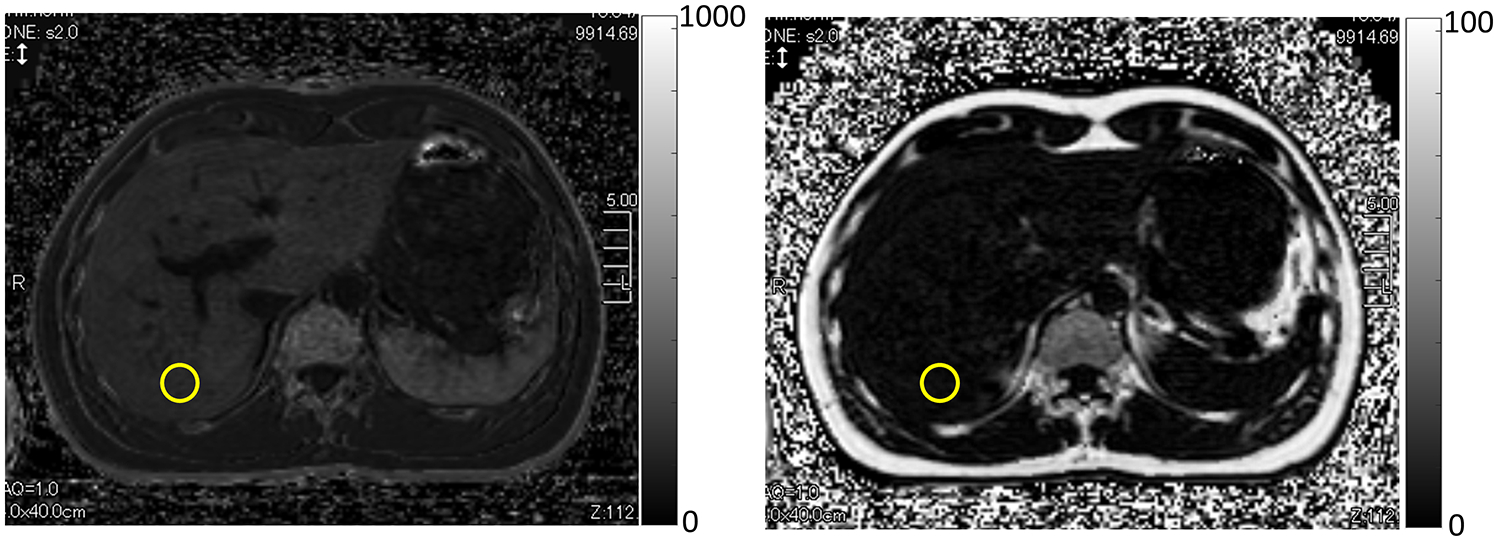

Figure 4.

Automatic inline reconstruction of the (left) R2* map (s−1) and (right) PDFF map (%) in a 42-yr old male using Canon Medical’s Fat Fraction Quantification (FFQ). ROI measurements (yellow circles) indicate an average R2* of 115 s−1 and PDFF of 3.42%. Data are acquired on a 3T Vantage system (Canon Medical Systems Corporation, Otawara, Japan) using a 3D gradient-echo, six-echo sequence. Maps may be shown in greyscale or color (not shown).